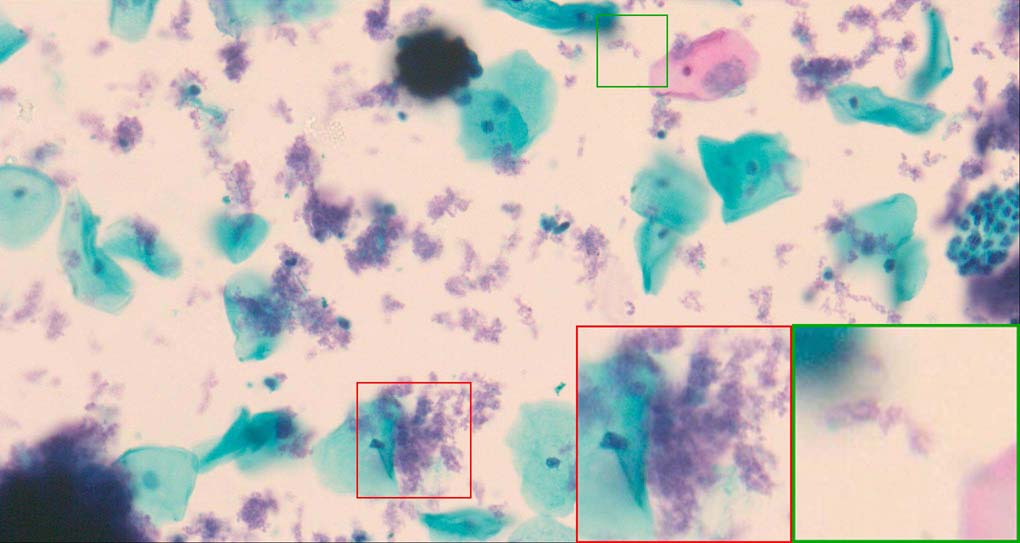

A good image fusion method should contain the following properties. First, it preserves both the details of small size objects and the integrity information of large size objects in the fused image, even in the case of the size of the interested objects varying largely in the image. For example, the cervical cell images from the microscope contain both small size isolated cells and large size agglomerates, which are both useful for cervical cytology [5]. Second, it should be efficient enough to handle large-scale data. For instance, it needs to process thousands of fields of view (FoV) in an acceptable time for the whole slide scanning in digital cytopathology [6], which requires to fuse a series of high resolution images captured at each FoV in a very efficient way. Third, it does not produce obvious artifacts. Despite being studied extensively, to our best knowledge, existing fusion methods may not meet these requirements simultaneously.

To demonstrate the effectiveness and efficiency of the proposed image fusion method , we conduct a set of comparative experiments on three image datasets. The first is composed by 8 pairs of multi-modal medical images and the second one contains 15 pairs of multi-focus gray or color natural images. These two datasets are often used in many related papers and some examples are shown in Figure 3(a) and Figure 3(b). The third one is a new multi-focus cervical cell image dataset collected by ourselves, which consists of 15 groups of color images and each group contains a series of multi-focus cervix cell images with size of or , etc. Some source examples are shown in Figure 3(c). Our source code implemented in C++ along with the new multi-focus cervical cell image dataset is available online.

Figure 9, Figure 10 and Figure 11 show the comparative fused results of the multi-focus cell images shown in Figure 3(c). For clarity, we also present a closeup view in the right-bottom of each sub-picture in Figure 9 and Figure 10. As shown in the close-up views of Figure 9, the fused images based on DSIFT, IM, MWGF and BF methods are extremely blurred in the boundary and fail to keep the details of cell nucleus. Furthermore, the DTCWT and NSCT based methods produce halo artifacts in the fused images, while GFF and CNN based methods fail to preserve the small cell nucleus. LP-SR based method nearly works fine which keeps the most of the details of the small size cells, but the integrity of the clustered large size cells is damaged. Fortunately, in our proposed method, the integrity of the clustered large size cells is preserved and most of the isolated small size cells are maintained from the original images, which demonstrates the best visual quality.

Similarly, as shown in the close-up views of Figure 10, the fused images from DSIFT, IM, MWGF and BF are blurred and lose some nucleus details, while the results from DTCWT, GFF, CNN and NSCT produce halo artifacts. LP-SR based method can keep details well but also produces halo artifacts and other noise. Our method can preserve the focused areas of different source images well without introducing any artifacts. For the example illustrated in Figure 11, the fused images generated by DSIFT, DTCWT, IM and NSCT all fail to preserve the focused areas of different source images and result in extremely blurred images. The GFF, CNN, MWGF and BF based method introduces a lot of color distortion of the nucleus regions and the obvious halo artifact. The result of LP-SR based method is close to the one of our method but introduces some odd color distortion. Again, our method produces fused image which can preserve the focused areas of different source images well without introducing any artifacts.